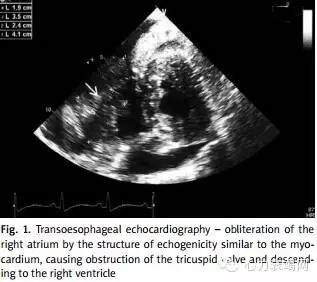

一位74岁女性病人因劳累性呼吸困难和持续2月的发烧入院。入院初期,该患者的体格检查除体温37.6℃外余无异常。实验室检查异常结果包括:Hb 10.5g/dl,WBC 10.6x10^9/L,CRP 71mg/l,ESR 47/86mm,AST 46 IU/l, ALT 74 IU/l, and GGTP 128 IU/l。心电图示窦性心律90次/分,II, III, aVF, and V3-V6导联T波压低。胸片示心脏肥大。经胸超声和经食道超声示右室一大肿物(图1)。心脏CT示浸润性结节,心包腔内心包积液,纵膈淋巴结肿大(图2A、2B)。3月前患者因房颤住院时经胸超声检查未发现右房肿物。